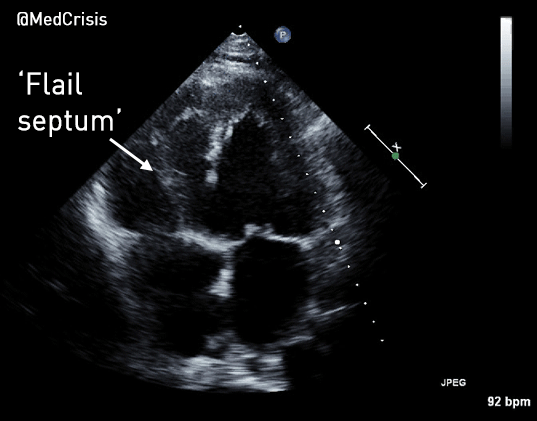

Parasternal long axis view: The septum is moving in an unusual jerky fashion and something can be seen in the RV. Despite left ventricular function appearing reasonable, the aortic valve is not opening much suggesting cardiac output is low.

The LV function is hyperdynamic. The infero-basal septum is tethered near the mitral and tricuspid valves but highly mobile, creating a large VSD. The right ventricular free wall appears to bulge out and the RV is almost akinetic.